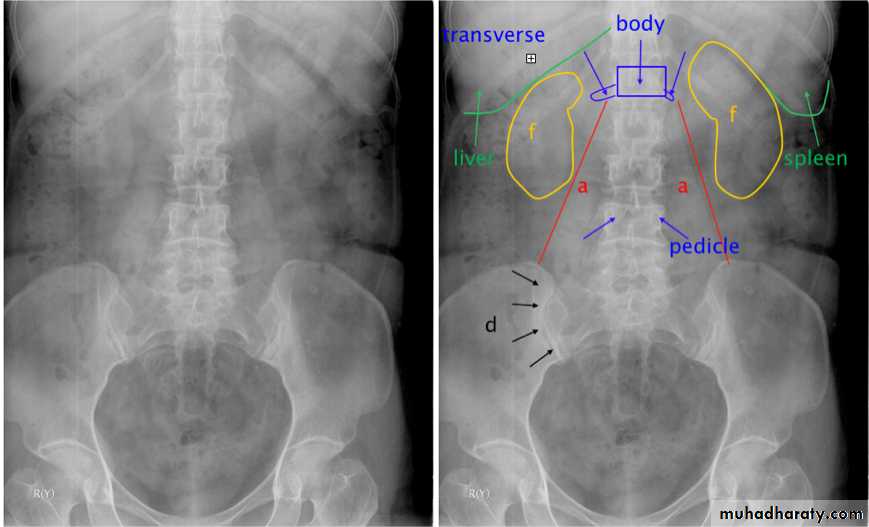

KUB

The post contrast series:

IV access is required for administration of the contrast material.The contrast dose is usually instilled at a fast (bolus) rate.

The calyces are usually not visualised in <2 minutes following contrast administration - This is the NEPHROGRAM phase.

Serial images are taken at 5-20 minutes for visualisation of the PCS and ureters…This is the PYELOGRAM or EXCRETORY phase.

Lastly take a full bladder and a post-void film.